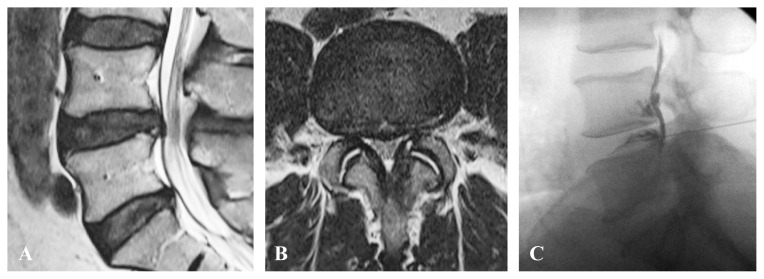

Abstract Image